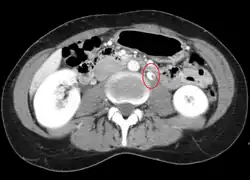

- Compression of the left renal vein (marked by the arrow) between the superior mesenteric artery (above) and the aorta (below) due to nutcracker syndrome